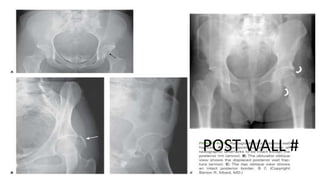

This document discusses different types of acetabular fractures including transverse, T-shaped, and both-column fractures. Transverse fractures are classified as transtectal, juxtatectal, or infratectal based on their location through the acetabular dome or fossa. Transtectal fractures require anatomical reduction while infratectal fractures may not need surgery depending on the pattern. T-shaped fractures disrupt the obturator ring and iliopectineal and ilioischial lines but do not involve the iliac wing, differentiating them from both-column fractures. CT scans can further classify fractures in the coronal or sagittal planes.